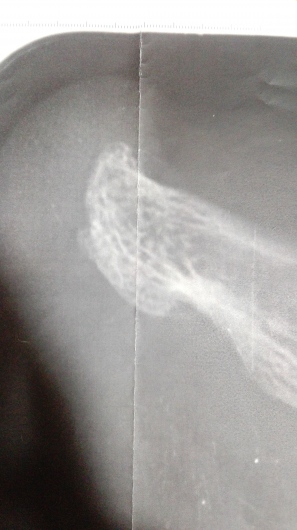

Podólogo especialista en Deportiva, Ecografía Diagnóstica e Intervencionismo y Cirugía Mis.

Ecografía diagnóstica